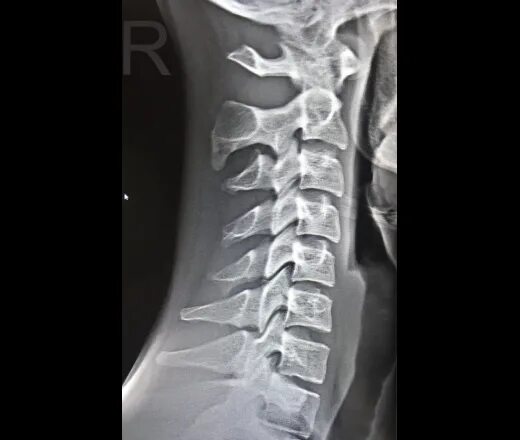

Перелом отростка l2